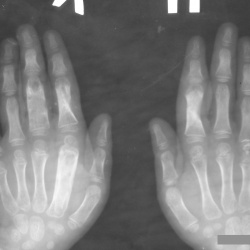

Доброго времени суток всем. Впервые столкнулась с такой картиной и засомневалась...Развейте, пожалуйста, мои сомнения.Клинику не знаю, принесли на описание снимки.

26.11.2011 - 12:20

Снимки ребенка нашего времени. С уважением Nikolas